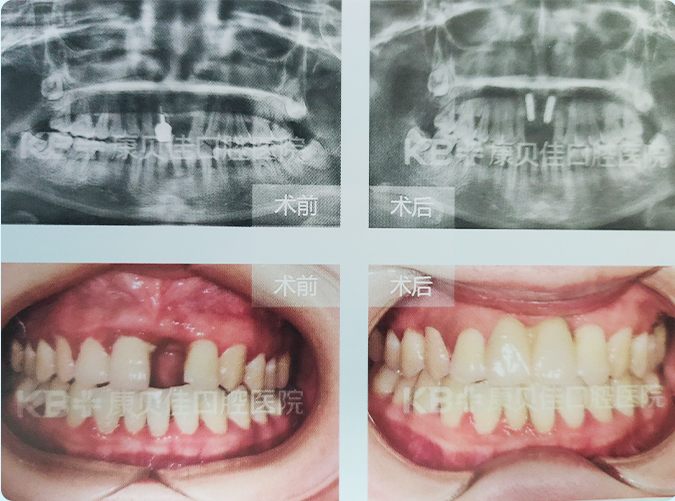

李女士

37岁

因外伤导致前牙松动在外院拔除,由于觉得门牙缺失影响美观及咀嚼,来院做种植修复,非常满意。

治疗方案:

上颌 种植2颗